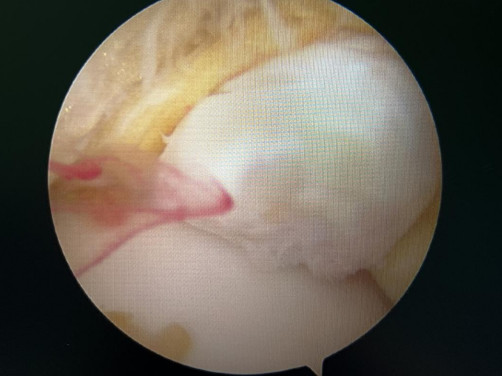

韌帶斷裂

幾經(jīng)輾轉,李先生來到廣安醫(yī)院就診,骨科中心主任羅軍副主任中醫(yī)師為他進行了詳細專業(yè)的查體,結合影像檢查,診斷為右踝關節(jié)不穩(wěn)(距腓前及跟腓韌帶斷裂)、右踝關節(jié)創(chuàng)傷性關節(jié)炎。羅軍主任帶領大家詳細分析病情之后,決定為他施行踝關節(jié)鏡下病變組織清理和距腓前韌帶、跟腓韌帶重建術。

醫(yī)生們在手術中發(fā)現(xiàn),李先生的右踝關節(jié)軟骨損傷明顯,踝關節(jié)前方及內(nèi)外側均有不同程度的骨質(zhì)增生,相互撞擊引起疼痛,同時距腓前及跟腓韌帶斷裂。手術醫(yī)生利用磨鉆,小心翼翼將引起撞擊的骨刺一一去除,然后,修復了損傷的關節(jié)軟骨,最后,為他完成了距腓前和跟腓韌帶的修復。

修復斷裂的韌帶